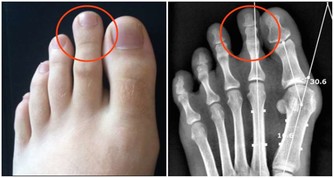

手麻與腳麻主要表現為局部刺痛、麻木或感覺異常,這可能是由於神經受到壓迫、血液循環不良或其他健康問題所引起。根據最新的健康研究,這些症狀不僅僅是短暫的不適,也可能是身體發出的緊訊,提醒我們及時關注潛在的疾病風險。

- 糖尿病引起的神經病變:糖尿病患者由於血糖控制不佳,容易導致周邊神經損傷,進而出現麻木現象。